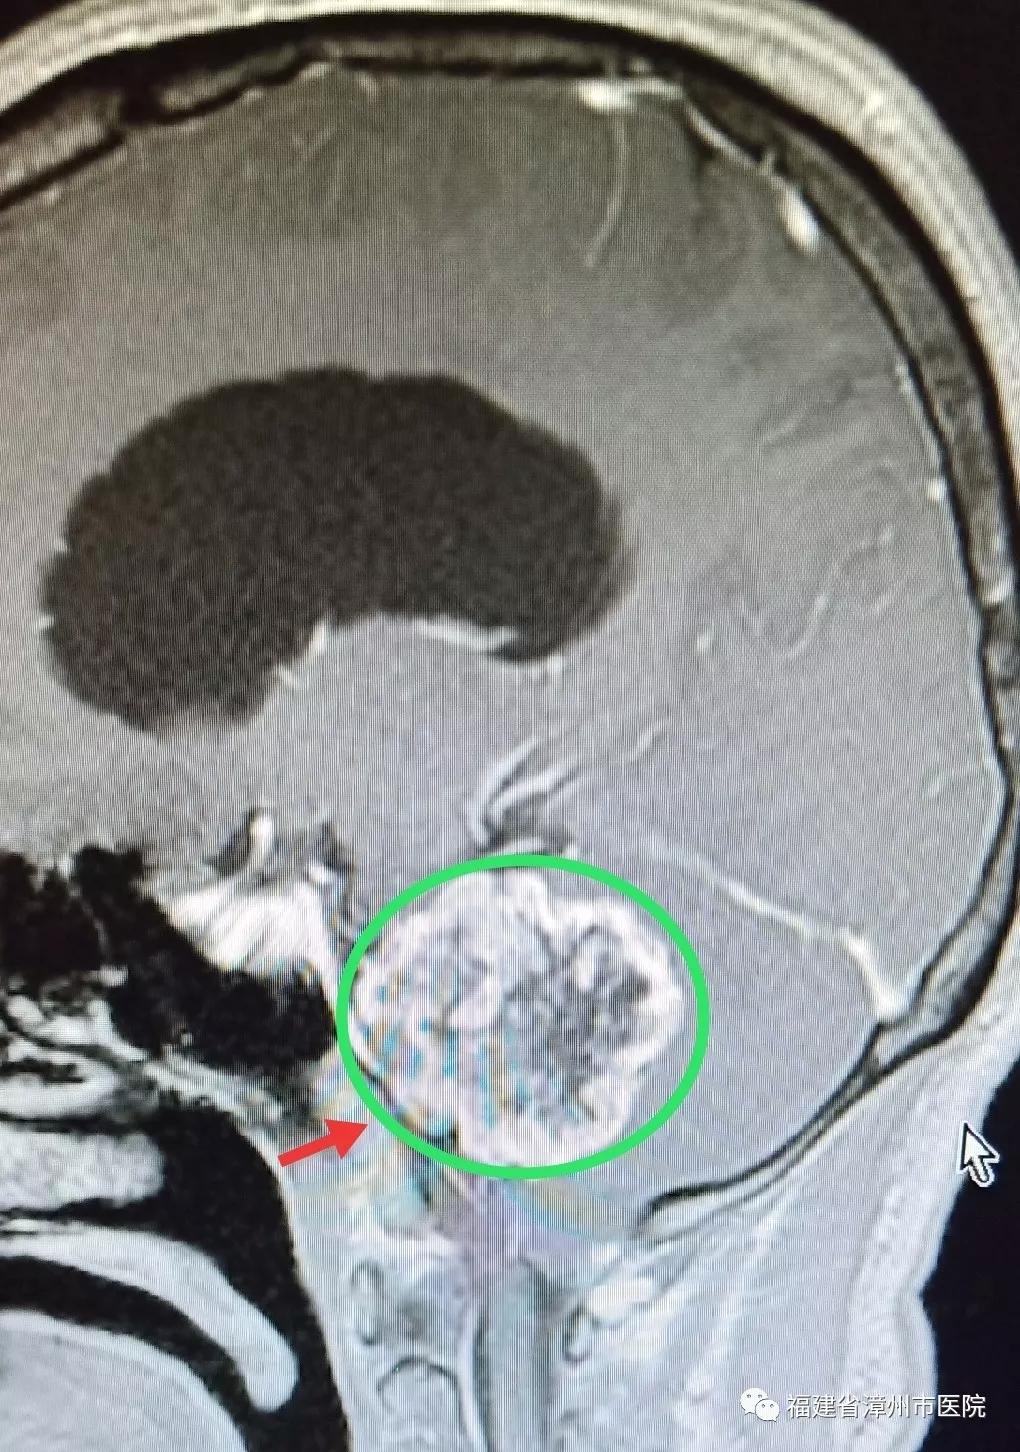

术前(肿瘤)